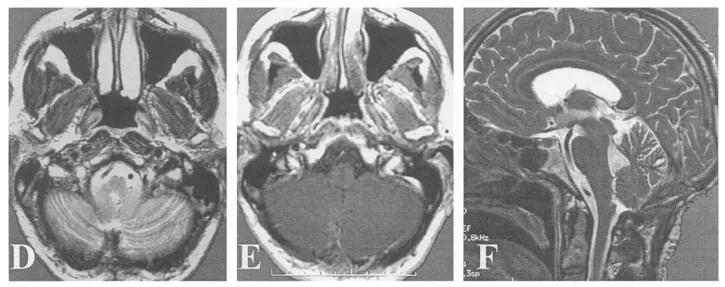

(E)小脑延髓外侧池内结构完整,箭头指示右侧椎动脉;

(D-F)术后6个月MR证实肿瘤全切。

(F)术后6个月患者临床状态良好。